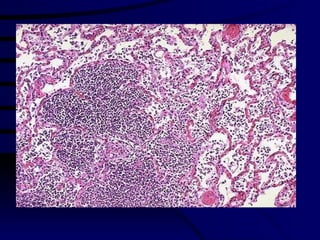

Clinical Details: 34 year , male Neck swelling, 2-3 months,  Fever, weight loss,  no other lymphadenopathy Lymphnode biopsy done

Lymphnode Biopsy Diffuse tumour Capsule

Lymphnode Biopsy Large cells Mitotic figures

Histiocytic/Tcell NHL Diffuse pattern – no follicles. Large cells with moderate cytoplasm Plenty of mitotic figures, Nuclei are vesicular prominent nucleoli Features suggest T-cell NHL – malignant lymphoma. Needs further marker studies for typing & management. cancer Chemotherapy.

Clinical Details: 34year , male Neck swelling, 2-3 months, Fever, weight loss, no other lymphadenopathy Lymphnode biopsy done

Lymphnode Biopsy Largecells Mitotic figures

Histiocytic/Tcell NHL Diffusepattern – no follicles. Large cells with moderate cytoplasm Plenty of mitotic figures, Nuclei are vesicular prominent nucleoli Features suggest T-cell NHL – malignant lymphoma. Needs further marker studies for typing & management. cancer Chemotherapy.